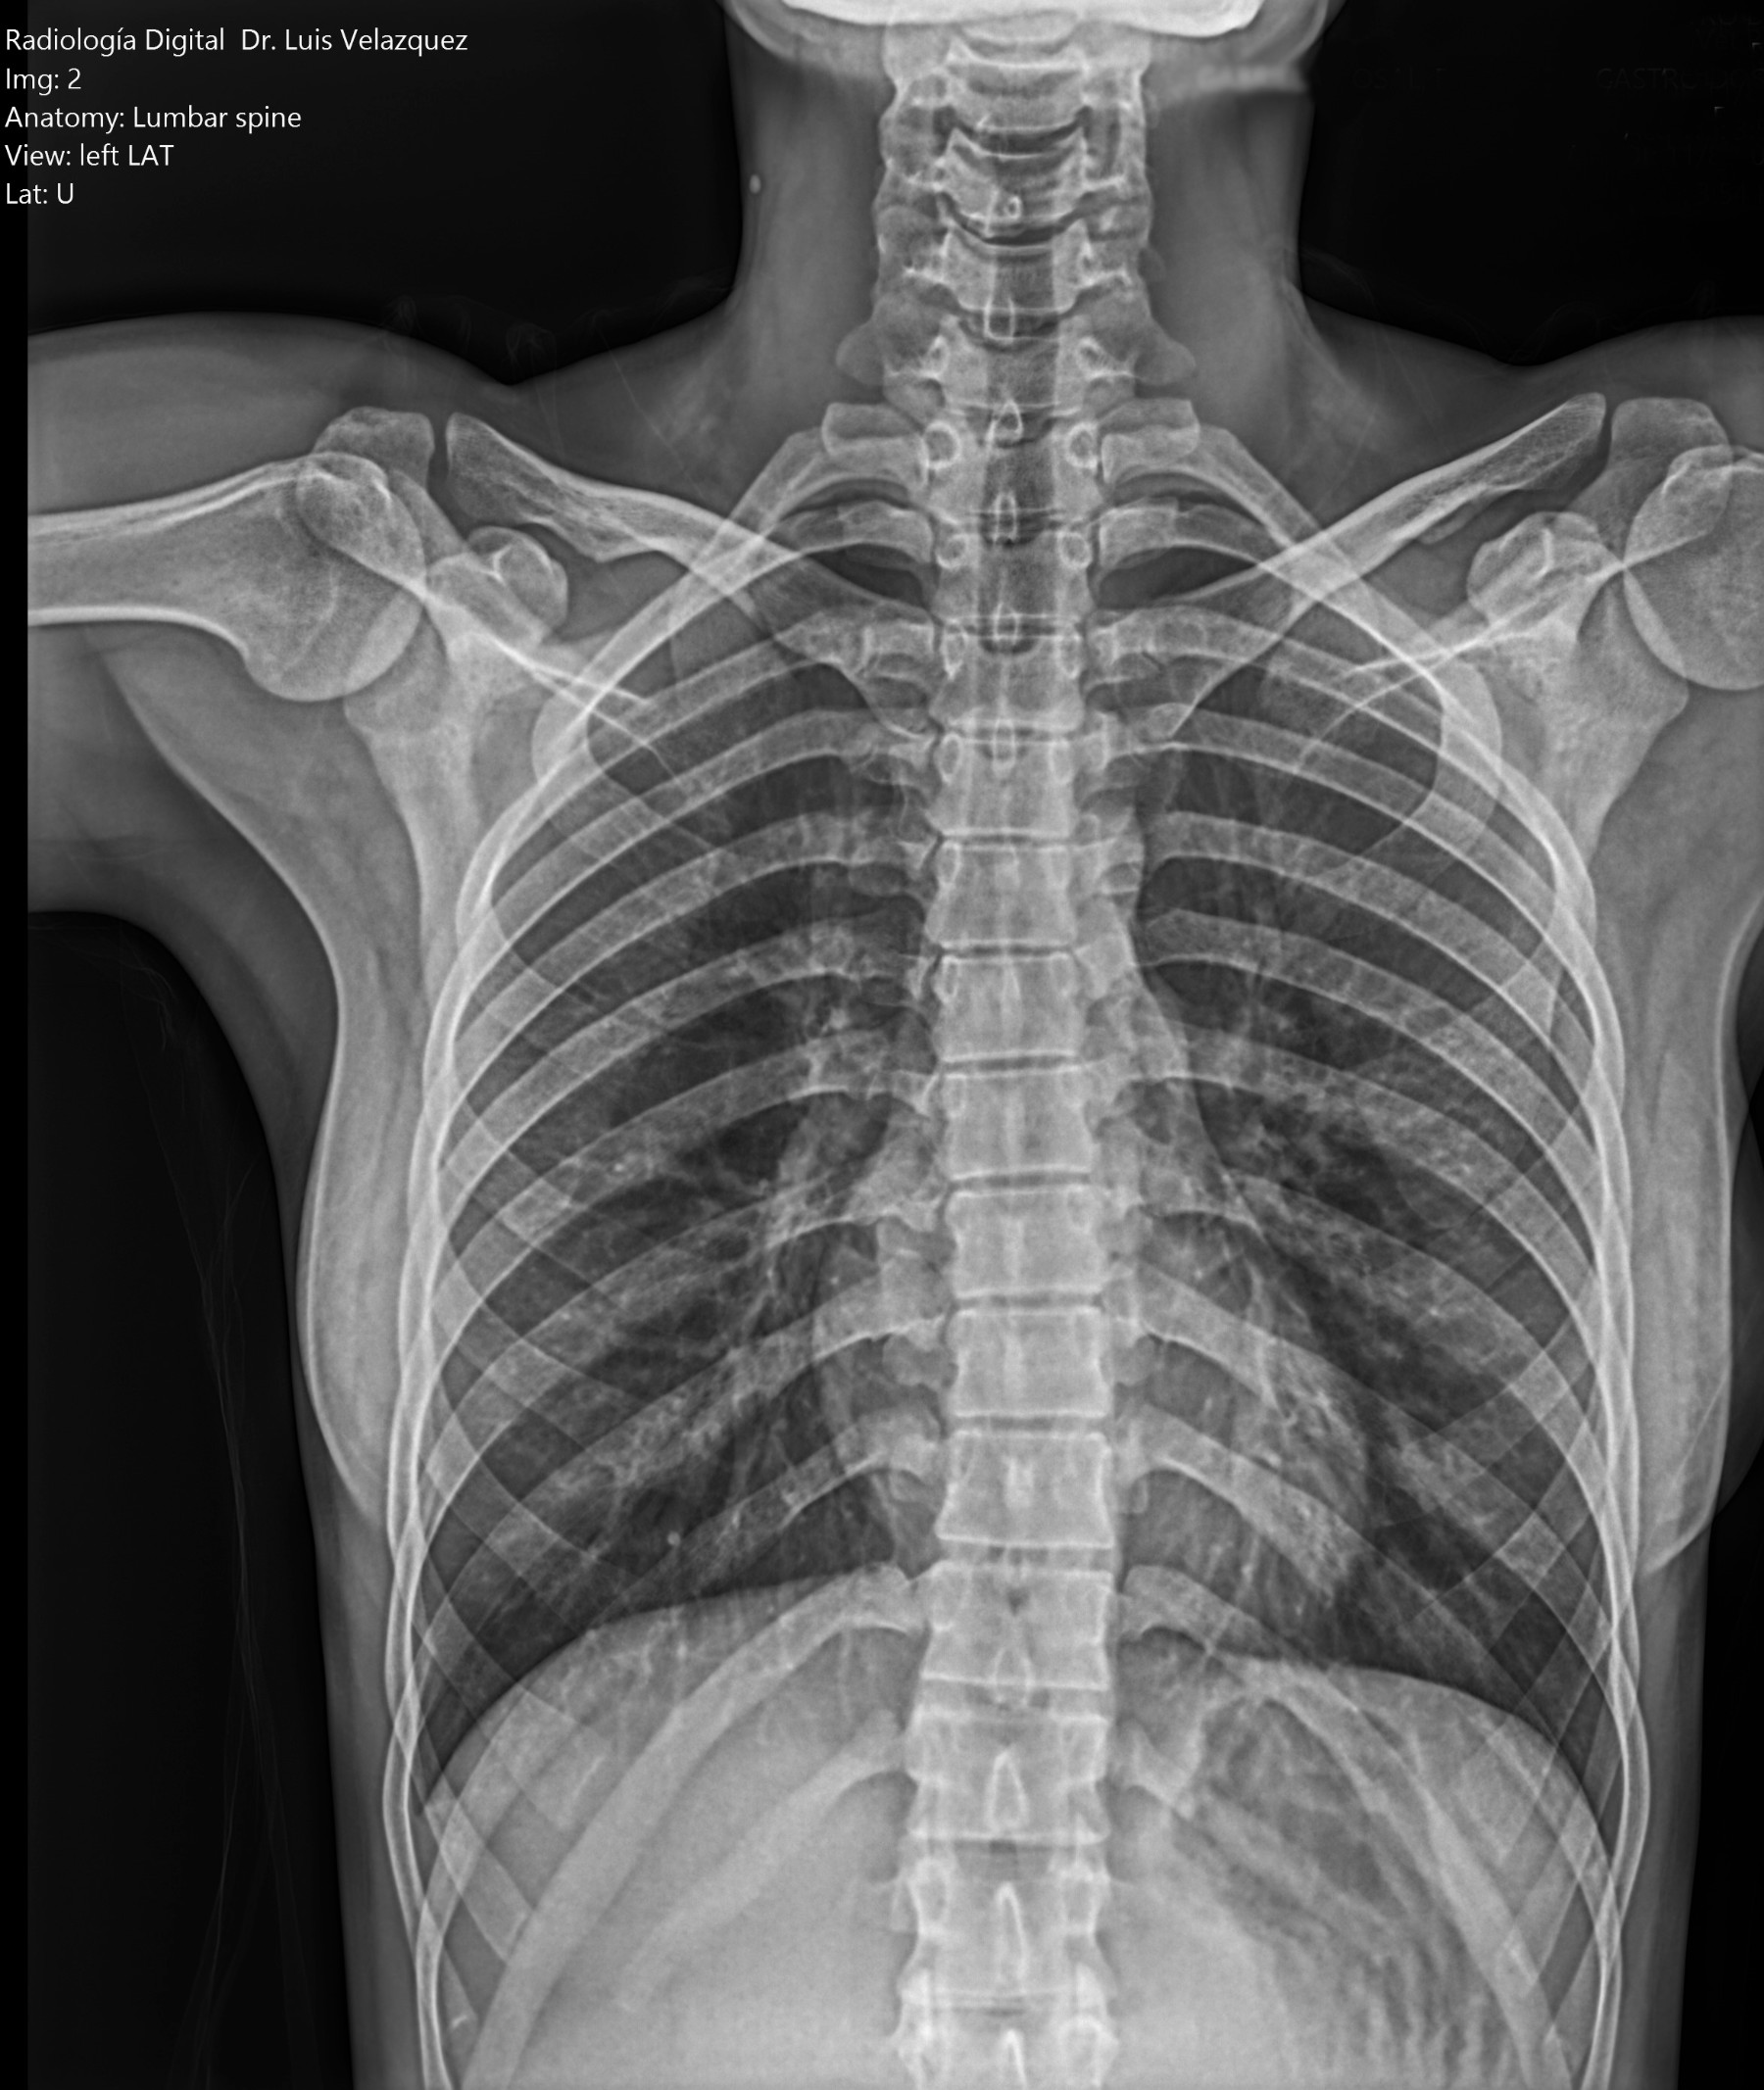

Cambios Térmicos en las Extremidades de Caballos,

Asociados a Golpes y su Evaluación por Termografía.

Los caballos de salto, en competencia, pueden derribar obstáculos y lastimarse. Si se golpean, no siempre claudican. Considerando al calor como un signo de inflamación, se evaluaron los cambios térmicos de 6 áreas de las extremidades torácicas y pelvianas de 23 caballos de salto en nivel de competencia de 1.05 a 1.60 m de altura, por medio de termografía durante 4 días de competencia (N=2208 áreas).